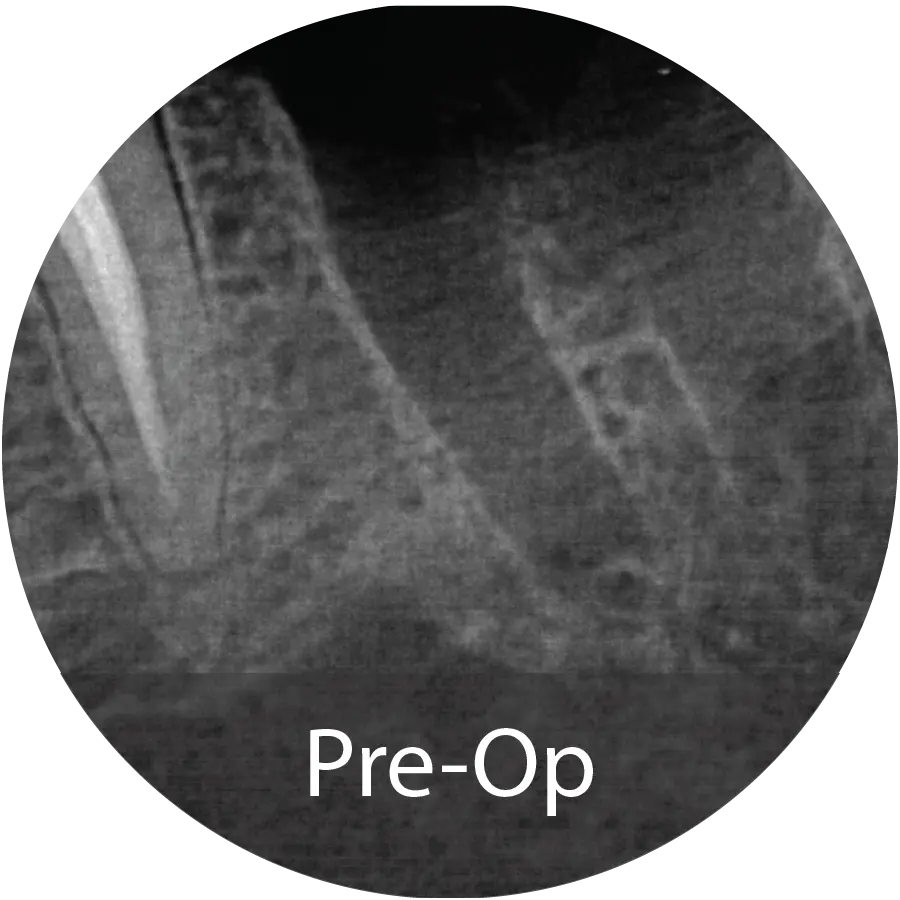

This 69-year-old male presented for extraction of tooth #4 for a failing root canal with decay. An alveolar ridge preservation procedure was performed utilizing INDUCE Oi-9®.

Fiber Matrix covered with an amnion chorion membrane.

Patient presented with complete healing at 5 months and implant placement took place.